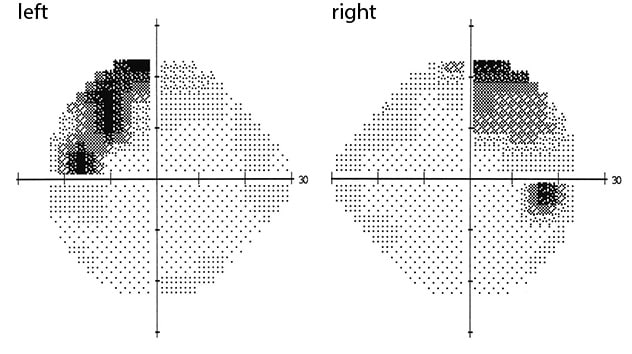

Visual field testing

Visual field testing

Visual field testing confirming bitemporal superior quadratanopsia.

A 44-year-old man with no significant past medical history presented with fatigue and a newly discovered 1.8 cm pituitary mass. He reported a six-month history of progressive fatigue and over the last two months had developed orthostatic hypotension, erectile dysfunction, polyuria and polydipsia. Along with these symptoms, he noted weight loss of 18 pounds, loss of appetite and fevers. The patient also experienced rhinorrhea with clear water-like nasal secretions that did not respond to nasal steroids for the last three weeks. On exam, he appeared ill and fatigued. Visual field testing confirmed a bitemporal superior quadrantanopsia.